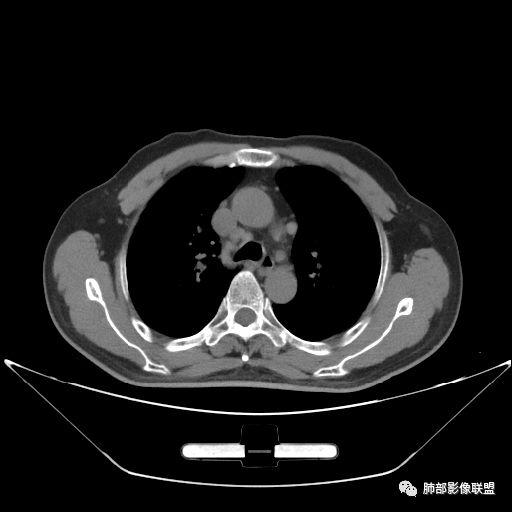

住院4天后行胸部增强CT

老年男性,因“咳嗽咳痰1月余。”入院。病程中咳嗽咳痰,咳黄白痰,间断咯少许鲜红色痰血。PPD阳性。胸CT:右肺中叶外侧段支气管管腔阻塞,大片实性病变,病灶边缘光滑,部分边缘膨隆,可见分叶,肺门及纵隔可见肿大淋巴结,并可见钙化。增强可见病灶明显强化,而且延迟强化明显,病灶内多发低密度区,内见血管影,血管变细、部分血管破坏。考虑恶性病变可能性大,鉴别慢性肉芽肿性病变。

胸CT:跨叶大肿块,主体在中叶,右中叶外侧段支气管阻塞,病灶部分边缘膨隆,可见分叶,部分边缘平直,肺门及纵隔可见肿大淋巴结。增强病灶不均匀强化,延迟强化明显,病灶内多发低密度区,内见血管飘浮,部分血管变细、模糊。考虑:恶性病变可能性大,大细胞?淋巴瘤?鉴别慢性肉芽肿性病变。

右肺中叶软组织肿块,外围向内生长,叶间胸膜向前内移位,肿块近肺门侧跨叶,中叶外侧段支气管截断,密度不均匀,双侧肺门及隆突下见肿大淋巴结,增强后呈中度不均质强化,肺动脉供血,多发坏死区,边界尚清,坏死区域内见结构,结合病史考虑恶性,鉴别诊断1结核,爬行征是沿支气管树分布,外宽,内窄,周围有卫星灶,内气管狭窄后扩张,此例沿叶间胸膜长轴分布,气管有截断,不典型。2炎性肉芽肿,符合的地方下方层面增强后延迟性轻度环形强化,不符临床无发热等急性感染病史,实验室指标不符,病灶周围渗出及慢性炎性改变有,不明显。

吴婧老师和南边老师都对该病例进行了深入分析。从支气管管壁的增厚,支气管狭窄后扩张,支气管粘液栓,病灶形态,到病灶不均匀强化及坏死彻底,到周边病灶及肺组织空气的潴留,加之纵隔内淋巴结肿大伴钙化等等,都支持慢性炎性病灶,尤其是结核。

墨西哥仙人掌征---结核        影像上结核灶,粗大的均匀枝干,推测是支气管囊状扩张引起的,在非支气管区,形成圆形坏死囊群;如果这些坏死比较稀薄,又遇到扩张支气管,就会形成粗大的“墨西哥仙人掌”。结核引起的支气管近端炎症纤维化,可以造成支气管阻塞,从而将干酪样坏死物封堵在管腔内。仙人掌主干内部应该是干酪为主,稀薄的,具有流动性,时间久了会出现钙化。